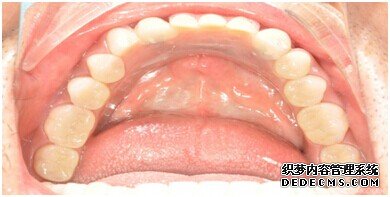

种植牙整个过程完成后,刘女士非常满意自己的牙齿,并且表示以后一定会遵照医生的嘱咐好好注意自己的口腔健康,每晚一定会好好刷牙,饭后漱口,当然也会注意保护这颗种植牙!